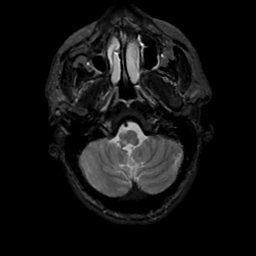

MR Study #13, May 19, 1991 -- Slice #7